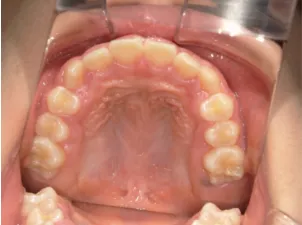

治療中④小2(8y2m)~小3(9y1m):QHとBHで拡大・アーチ形態の修正、ブラケットで前歯の並べ替えまで終了

| 行ったご提案・診断内容 | 成長期に行う治療と咬合治療をご提案 受け口用ファンクショナルアプライアンス(写真②③)からスタートし、小2以降で上下顎の拡大・歯列弓の形態修正・前歯の並べ直し(写真④)を行いその後、モノブロック(筋機能的咬合誘導)装置(写真⑤)へ移行し、受け口の再発予防と永久歯を適切な咬み合わせに誘導し、必要によりマルチブラケット法へ移行する治療方法を提案しました。 成長期治療(成長時期にお口の環境を整える治療) 2年生以降から 咬合治療 |

| 治療期間 | 12か月:受け口用ファンクショナルアプライアンス(写真②③) 12カ月:成長期治療の動的治療期間(写真④) 現在、成長の経過観察と咬合誘導中です(写真⑤~⑨) |